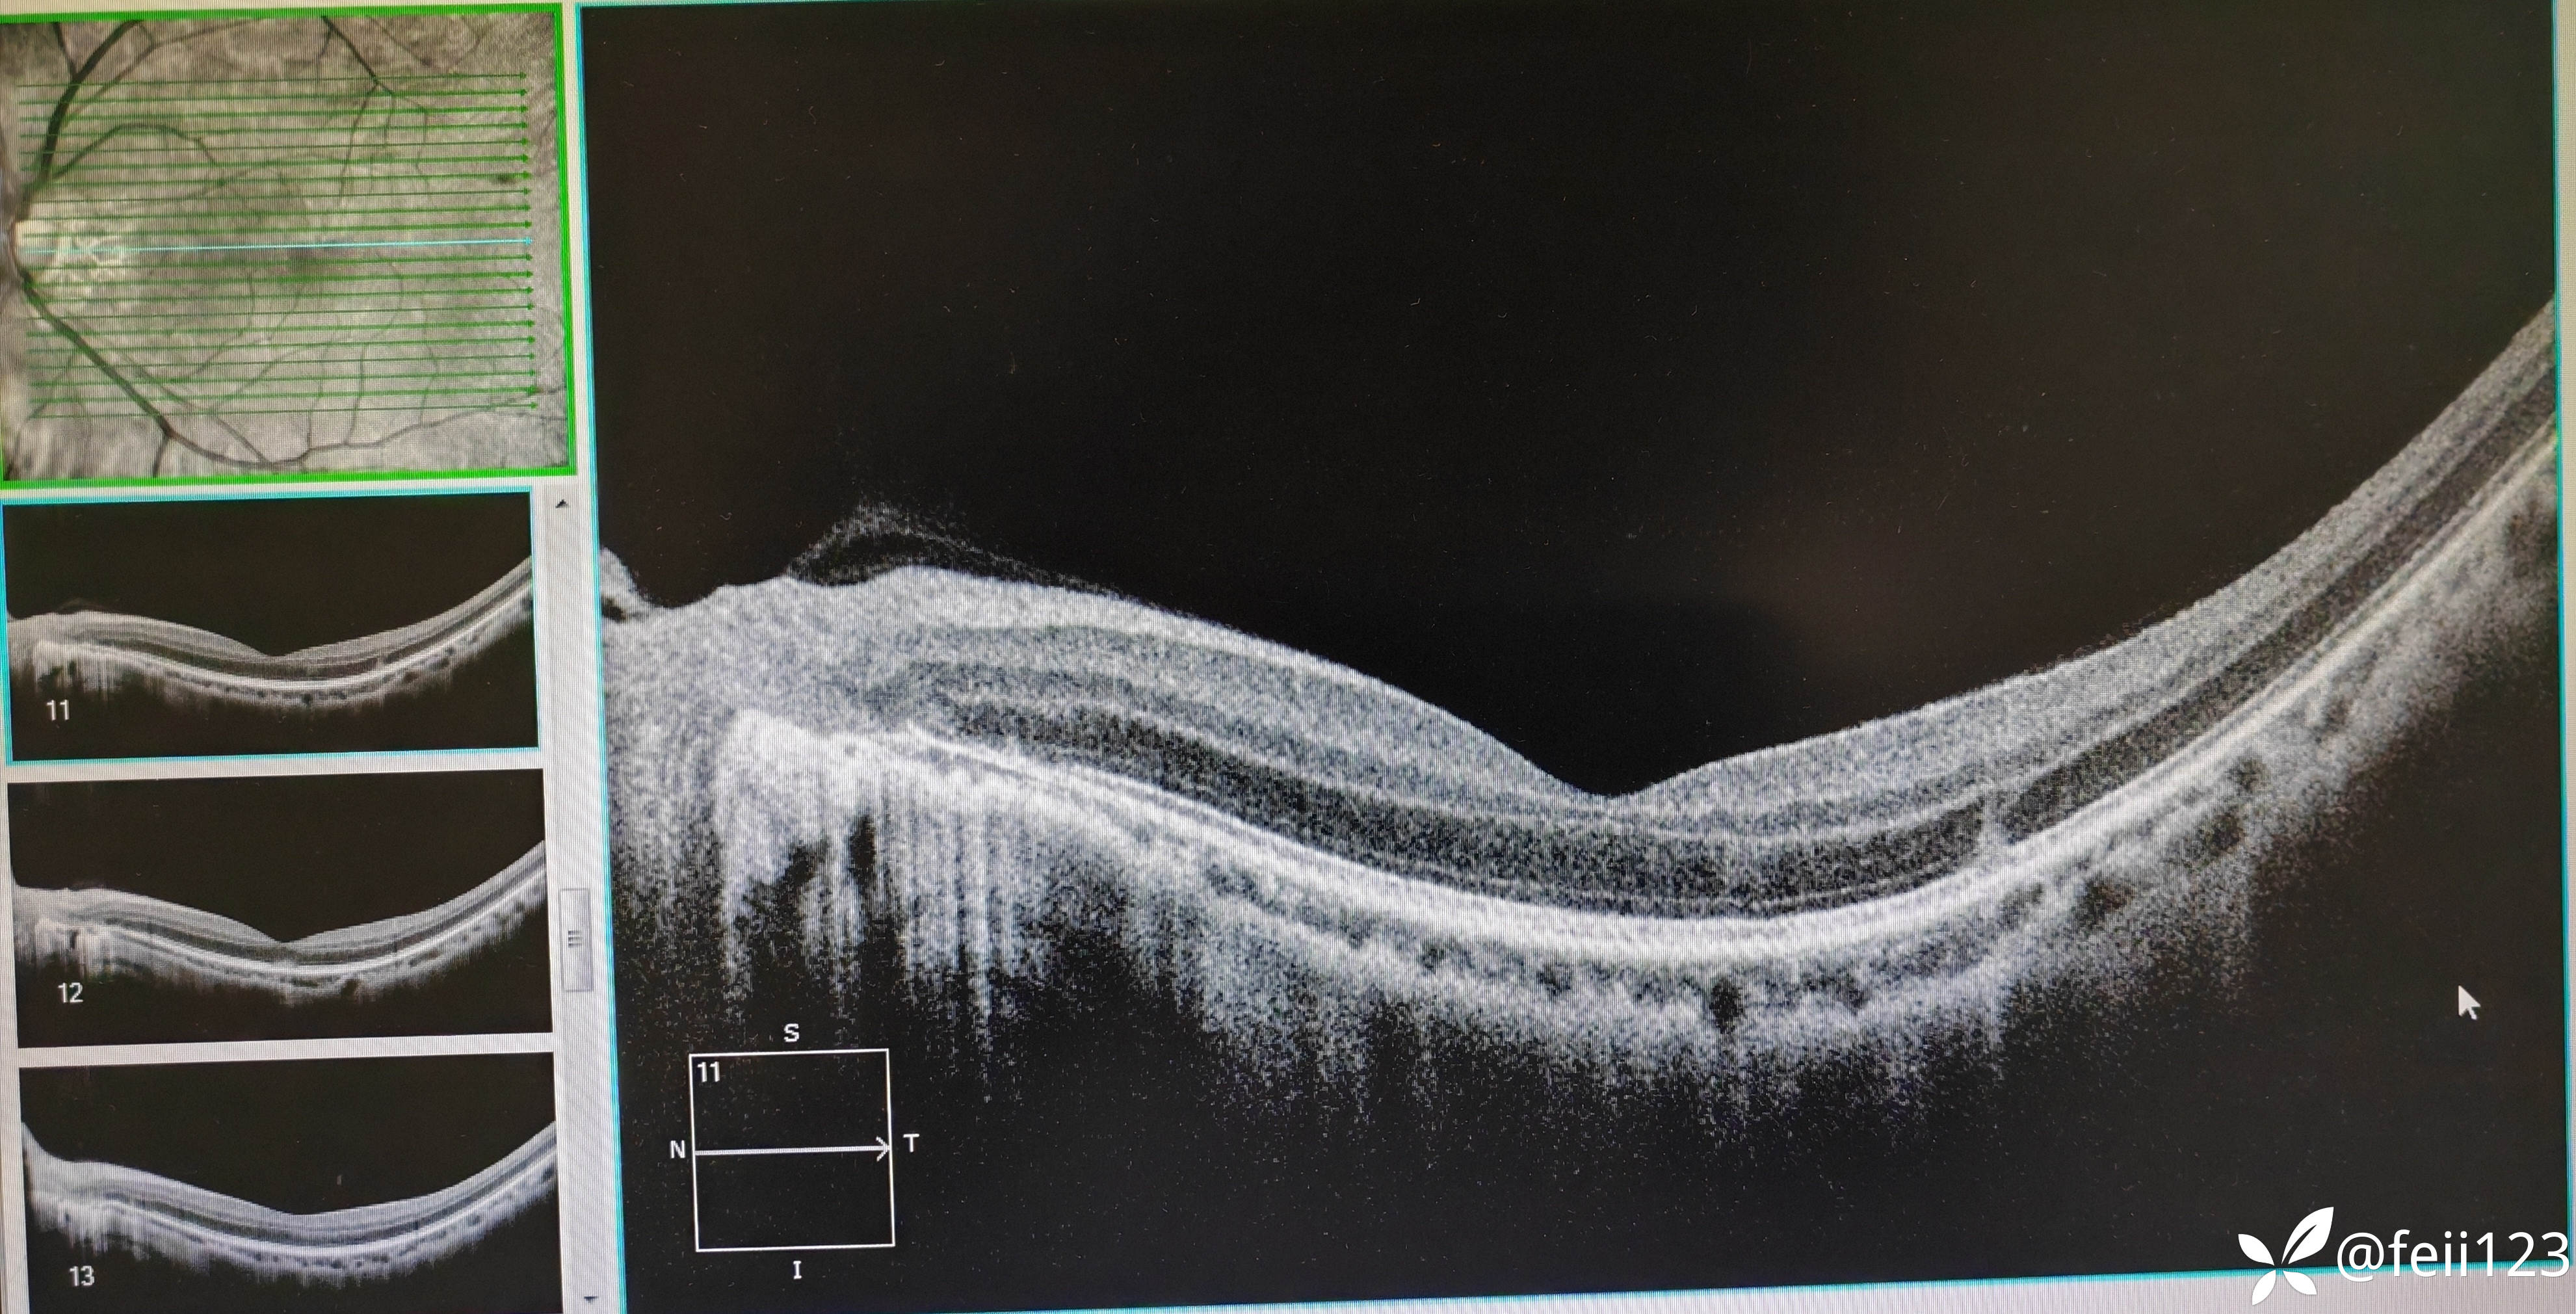

患者信息】:年轻男性30岁

【主诉】:左眼前黑点5天,无诉闪光感

【现病史及既往史】:无特殊,无全身病,中高度近视史

【检查】矫正视力右眼1.0左眼0.4,眼压正常15 16,眼前段未见异常,玻璃体清,眼底如图,左眼底可见后极部及鼻侧周边多个白点。

患者未完全确诊,想请教各位老师,这个患者的诊断,我考虑患者是白点综合症,但是AZOOR还是MEWDS还是其他比较有疑问,请大家指导